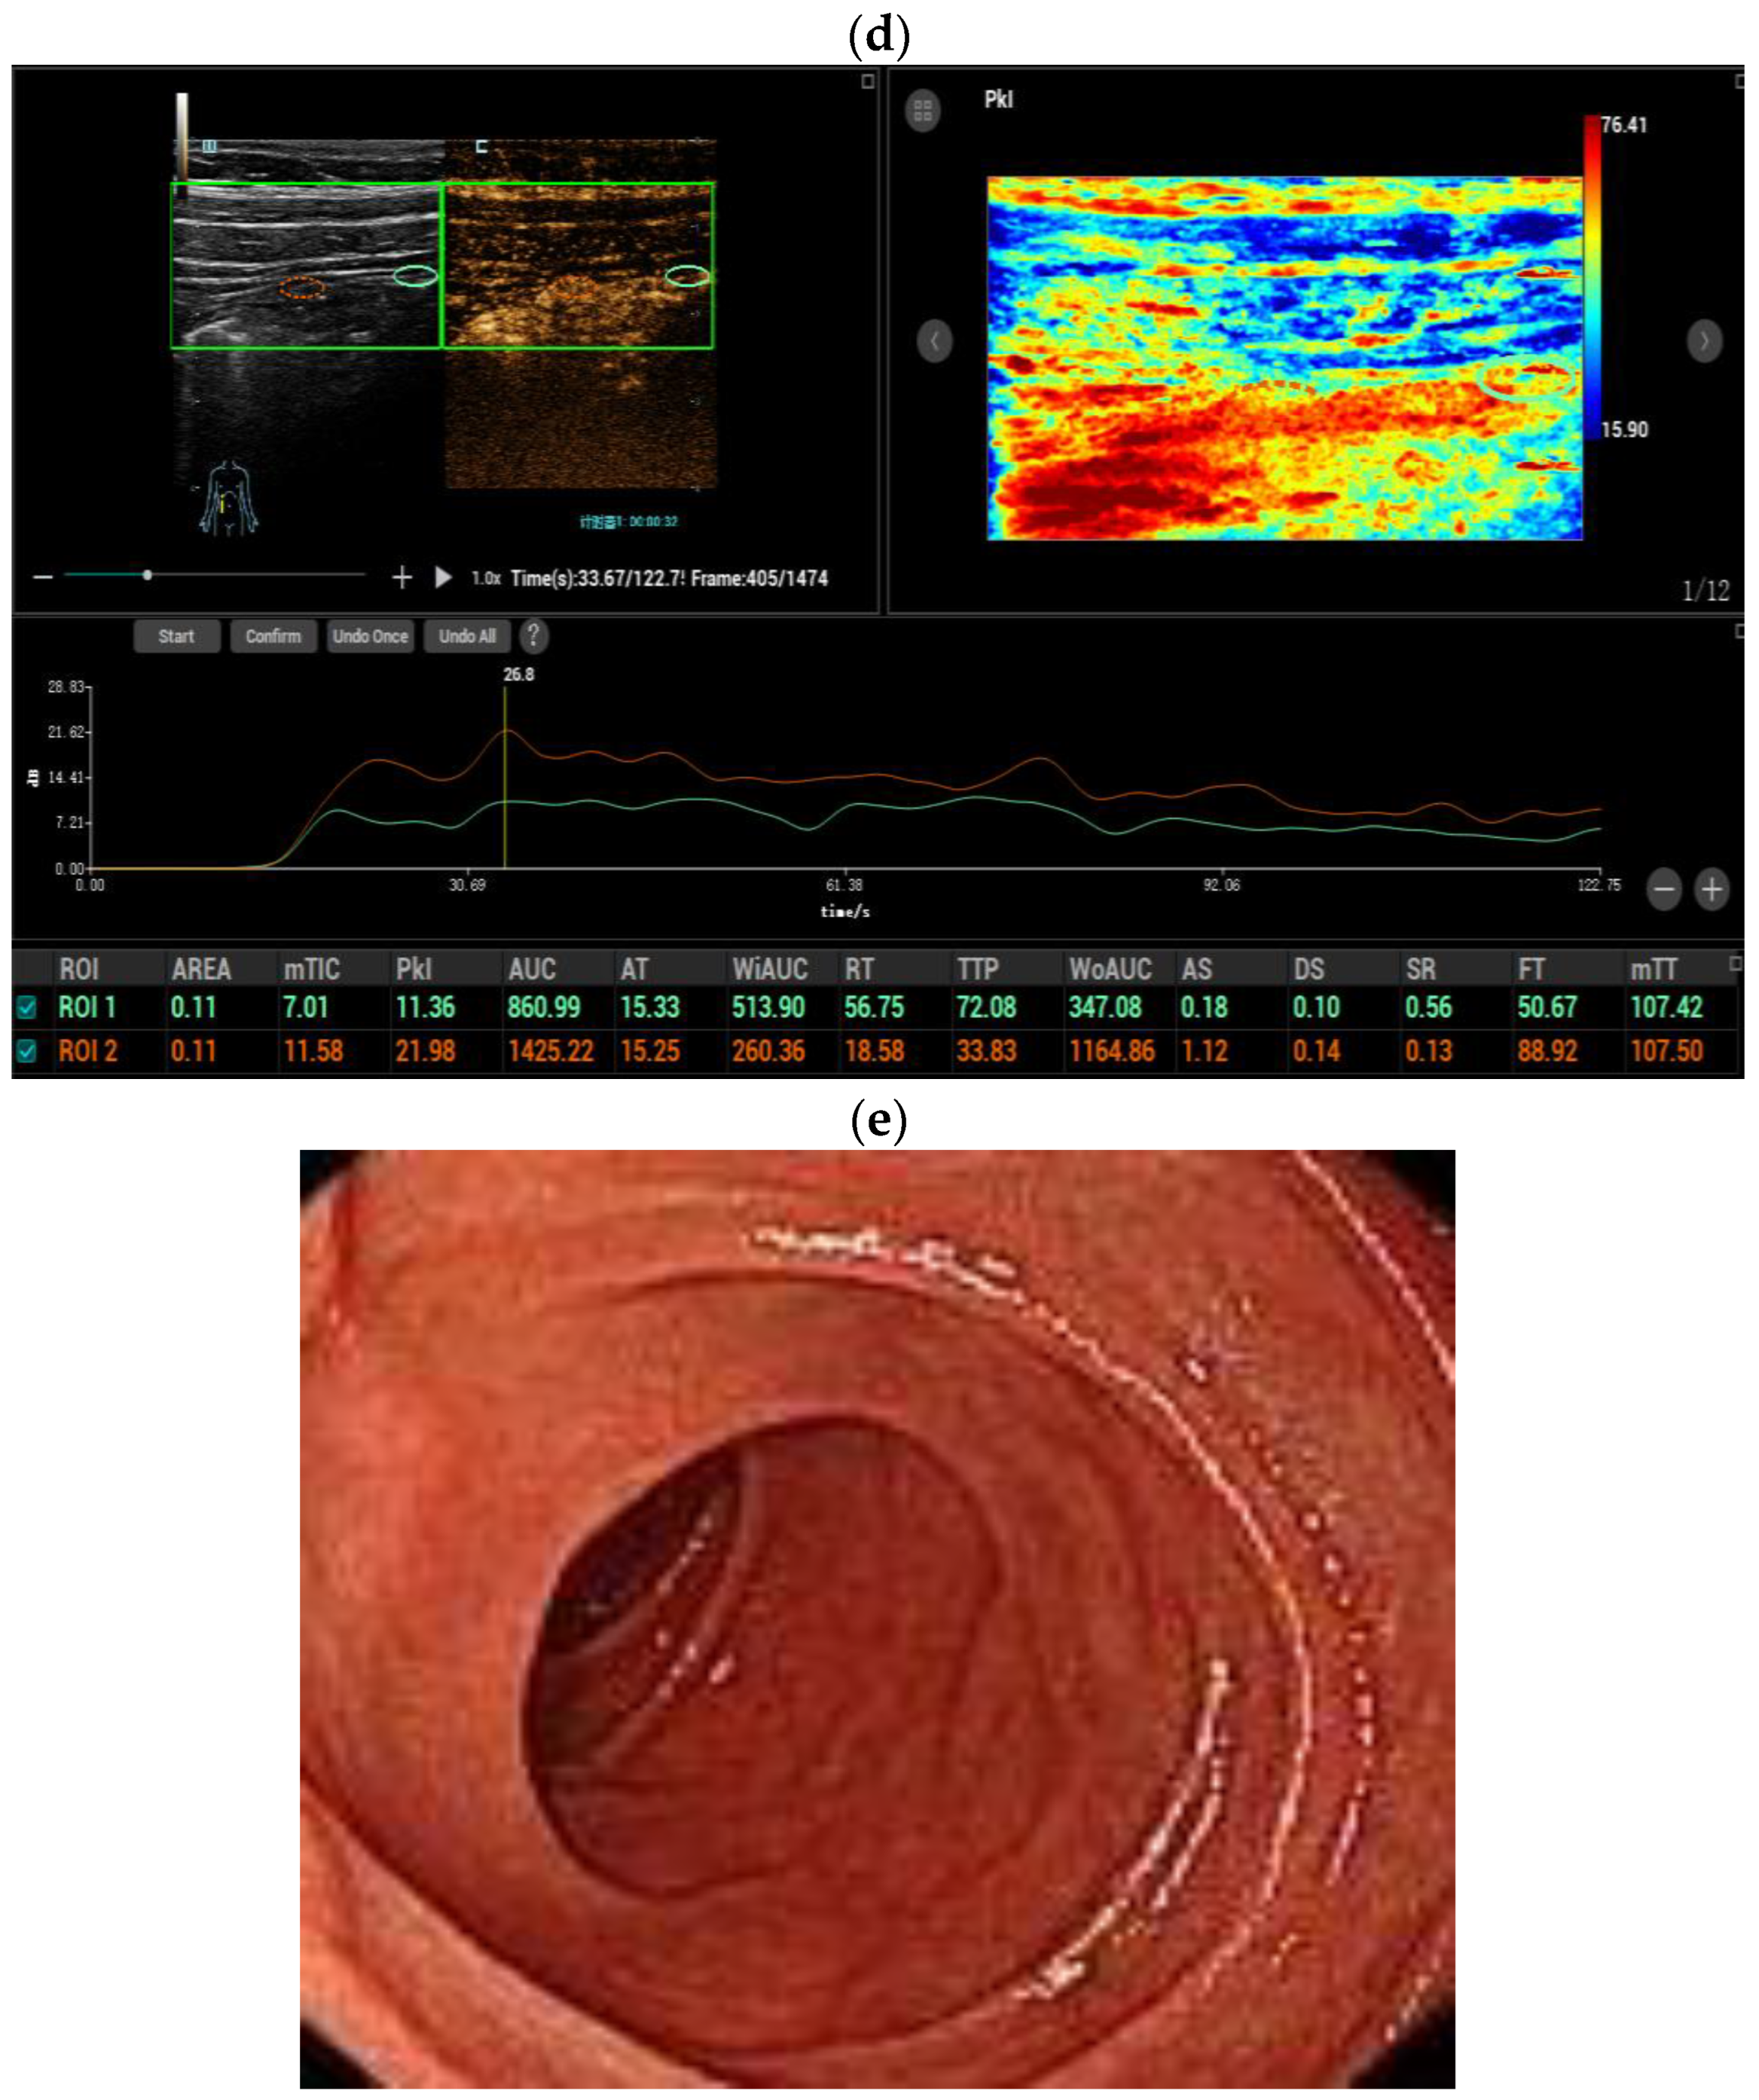

3.3. Dynamic Contrast-Enhanced Ultrasound (DCE-US) Quantitative Analysis

| CEUS enhancement | <0.001 * | ||

| Pattern I | 24 (61.5%) | 1 (7.7%) | |

| Pattern II | 10 (25.6%) | 3 (23.1%) | |

| Pattern III | 5 (12.8%) | 8 (61.5%) | |

| Pattern IV | 0 | 1 (7.7%) | |